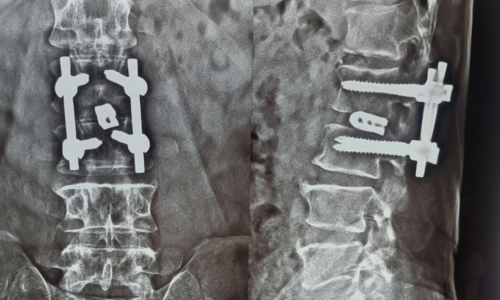

Cervical Myelopathy

Cervical Myelopathy Expert Care by Dr. Nitish Agrawal – Best Spine Surgeon in Pune Cervical Myelopathy is a serious spinal condition in which the spinal cord in the neck (cervical spine) becomes compressed. This compression is most commonly caused by degenerative changes in the spine, such as cervical disc prolapse,…